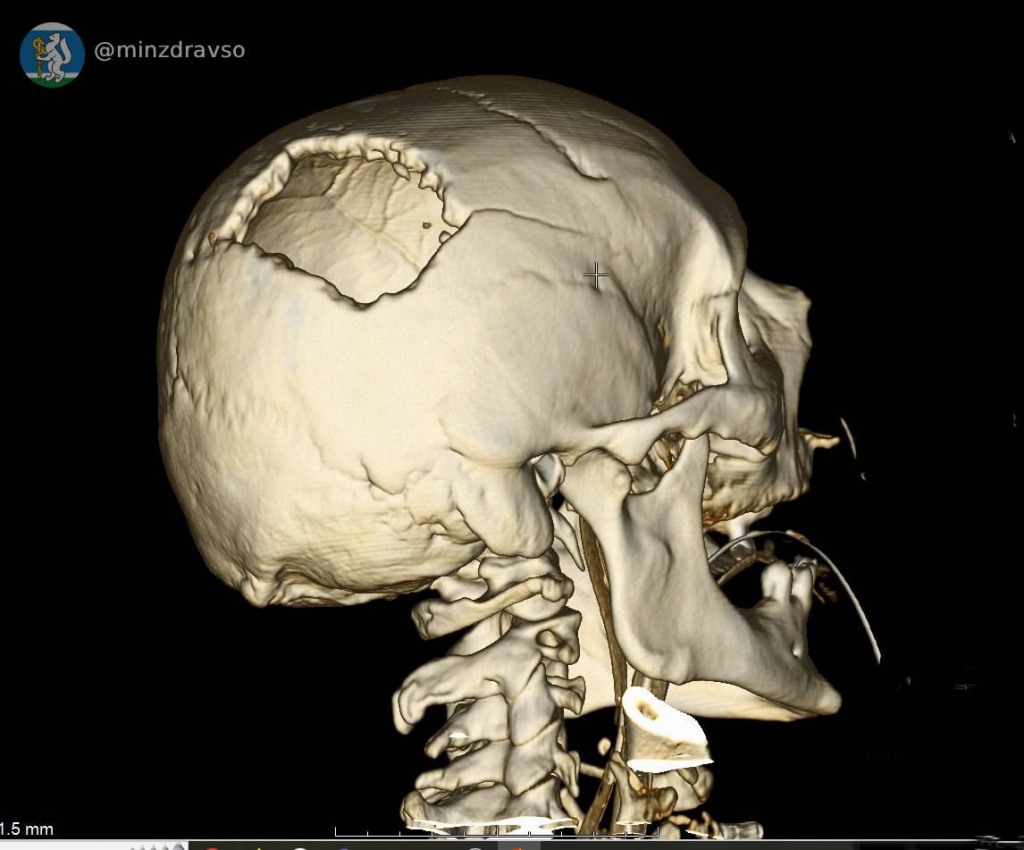

В Серове 57-летнего мужчину ударила стрела строительного крана, расколов ему череп. В критическом состоянии мужчина поступил в единственное на севере нашего региона стационарное отделение скорой медицинской помощи, действующее на базе Серовской городской больницы. Высокоточный компьютерный томограф помог быстро диагностировать травмы и выявить расположение повредивших мозг костных отломков, самый острый из которых мог в любую минуту стать причиной гибели пациента. Слаженное взаимодействие серовских реаниматологов позволило стабилизировать состояние пострадавшего.

Профильные специалисты из Екатеринбурга в ходе телеконсультации подтвердили необходимость перегоспитализации уральца в ближайший межмуниципальный медицинский центр. Мужчину экстренно доставили в Городскую больницу №1 Нижнего Тагила, где его ожидала операционная бригада. Нейрохирург Дмитрий Неволин, анестезиолог-реаниматолог Аслам Абдуев и операционная медсестра Нина Дмитриева удалили отломки костей, гематомы, восстановили целостность твёрдой мозговой оболочки.